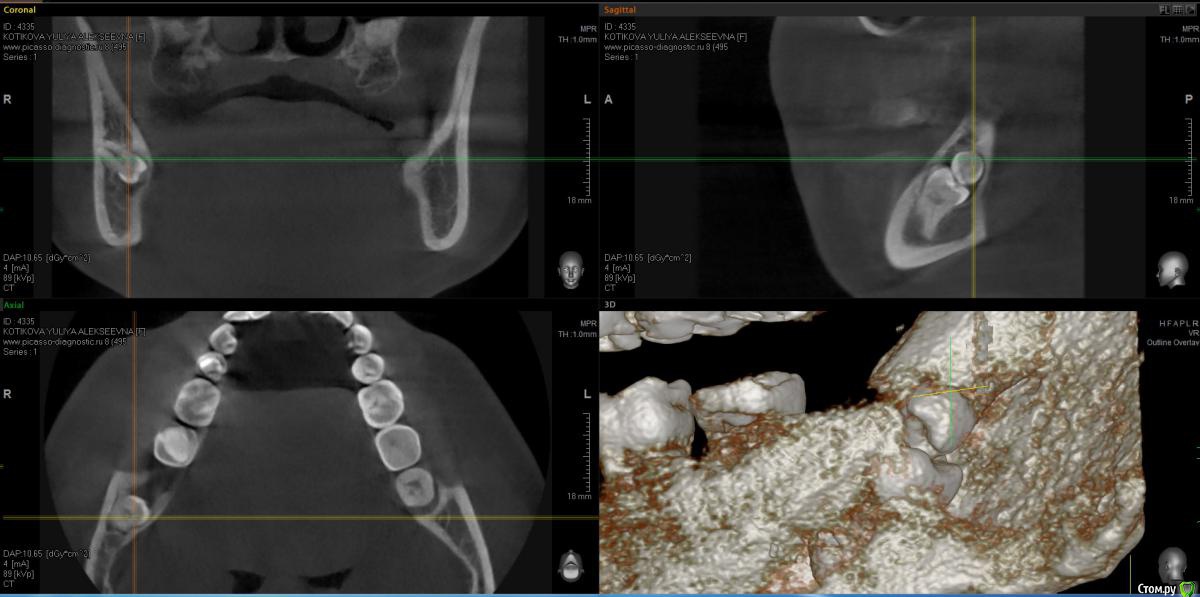

Kitten Опубликовано 20 декабря, 2014 Автор Поделиться Опубликовано 20 декабря, 2014 Я сделала ОПТГ и КТ. Ссылка на КТ ниже. Для тех, у кого нет возможности скачать файл полностью, приложила скриншоты. Жду ваши рекомендации. https://yadi.sk/d/3-GC2npldVBv4 Ссылка на комментарий

Kitten Опубликовано 14 декабря, 2014 Автор Поделиться Опубликовано 14 декабря, 2014 К/Т лучше делать для всей нижней челюсти или только для этого участка (8-9 зуб)? 1 Ссылка на комментарий

kladoffka Опубликовано 15 декабря, 2014 Поделиться Опубликовано 15 декабря, 2014 К/Т лучше делать для всей нижней челюсти или только для этого участка (8-9 зуб)? Всей. Поможет в дальнейшем планировать лечение и в других сегментах. Ссылка на комментарий